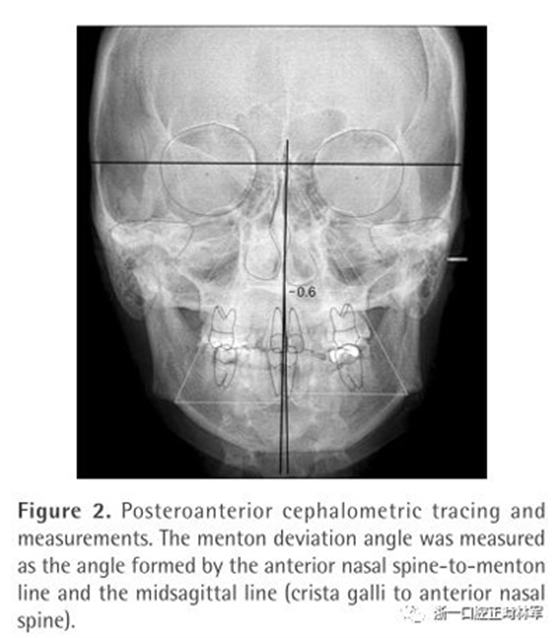

為了測量頦部偏移角度和唇線傾斜的關系,在拍正位片的時候,在兩個耳桿上都有金屬球來作為參考以確保FH平面和地面平行。頦部偏移角度為前鼻嵴-頦點連線與正中矢狀線的夾角(Figure 2)。